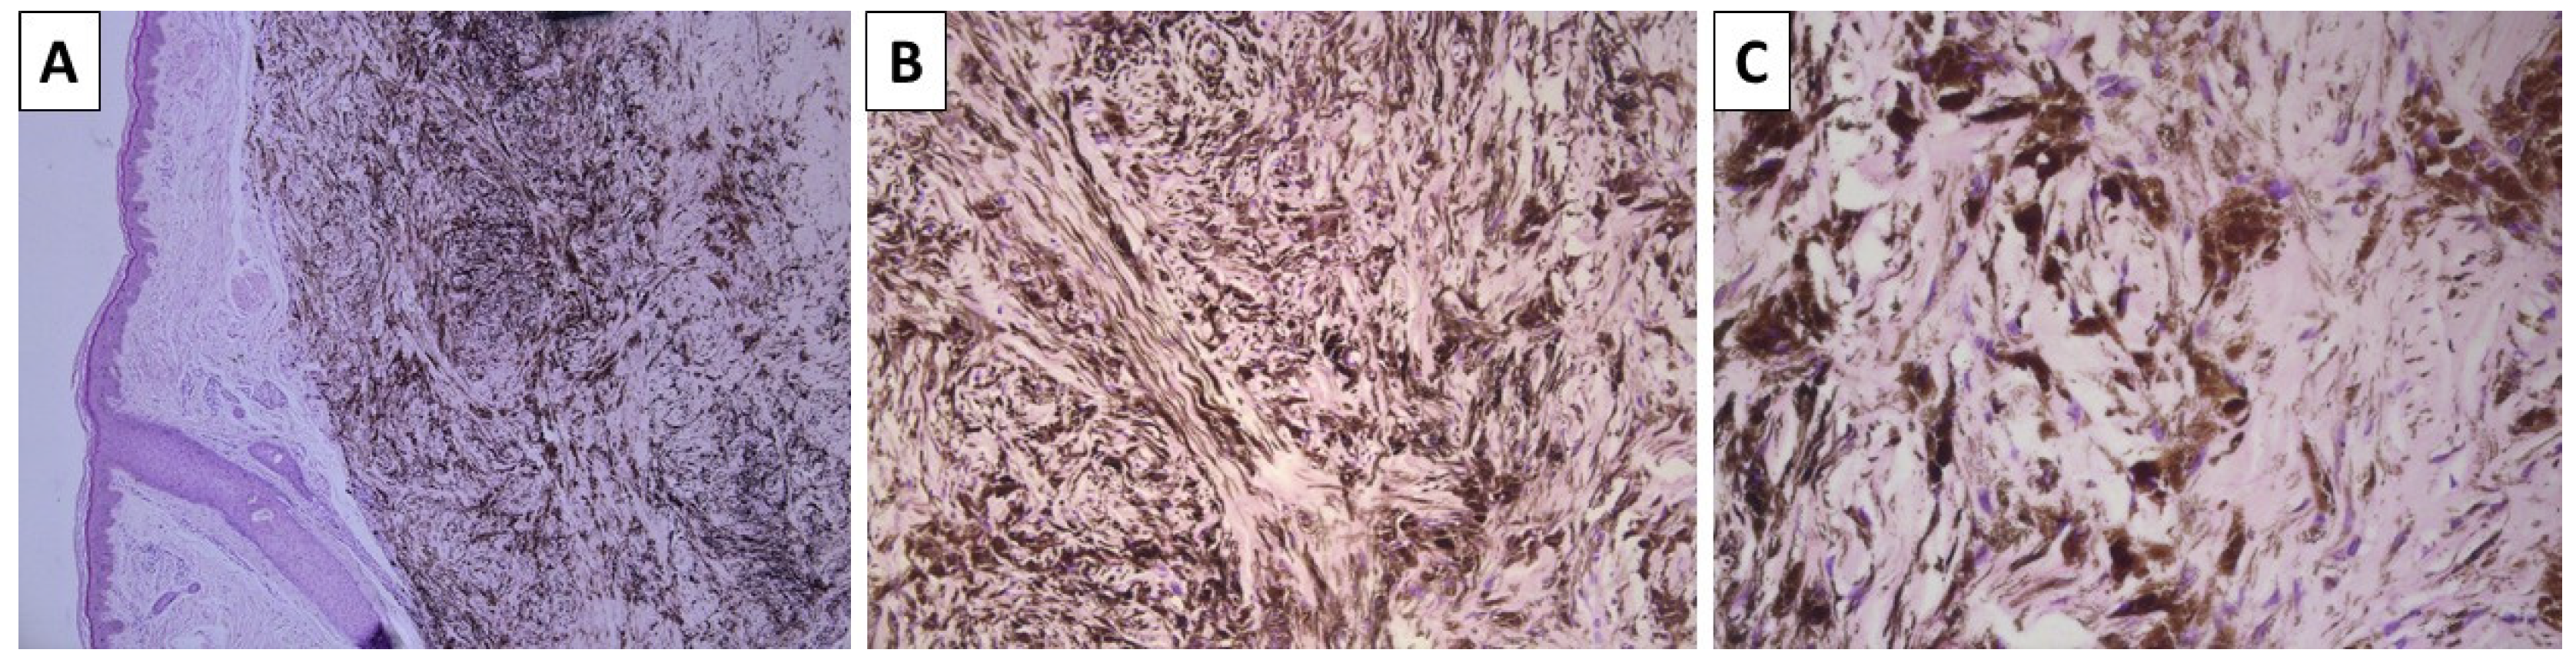

2.1. Cases 1 and 2—Conventional Dendritic Blue Nevus and Sclerotic Dendritic Blue Nevus